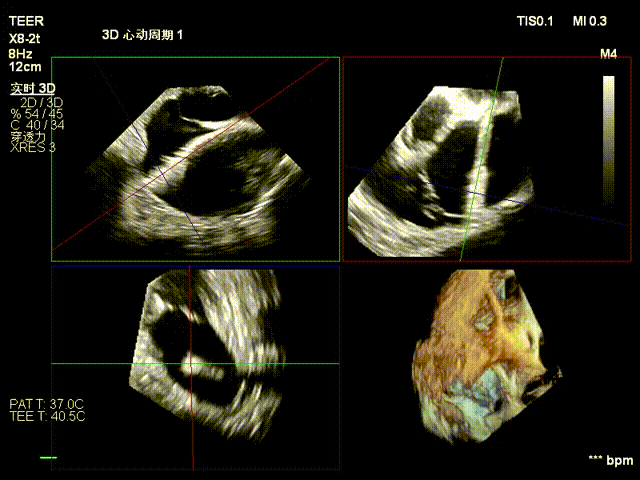

视频3:二尖瓣三维视图

图1、图2:2区瓣叶长度(前叶长度2.46cm,后叶长度1.15cm)及彩色血流